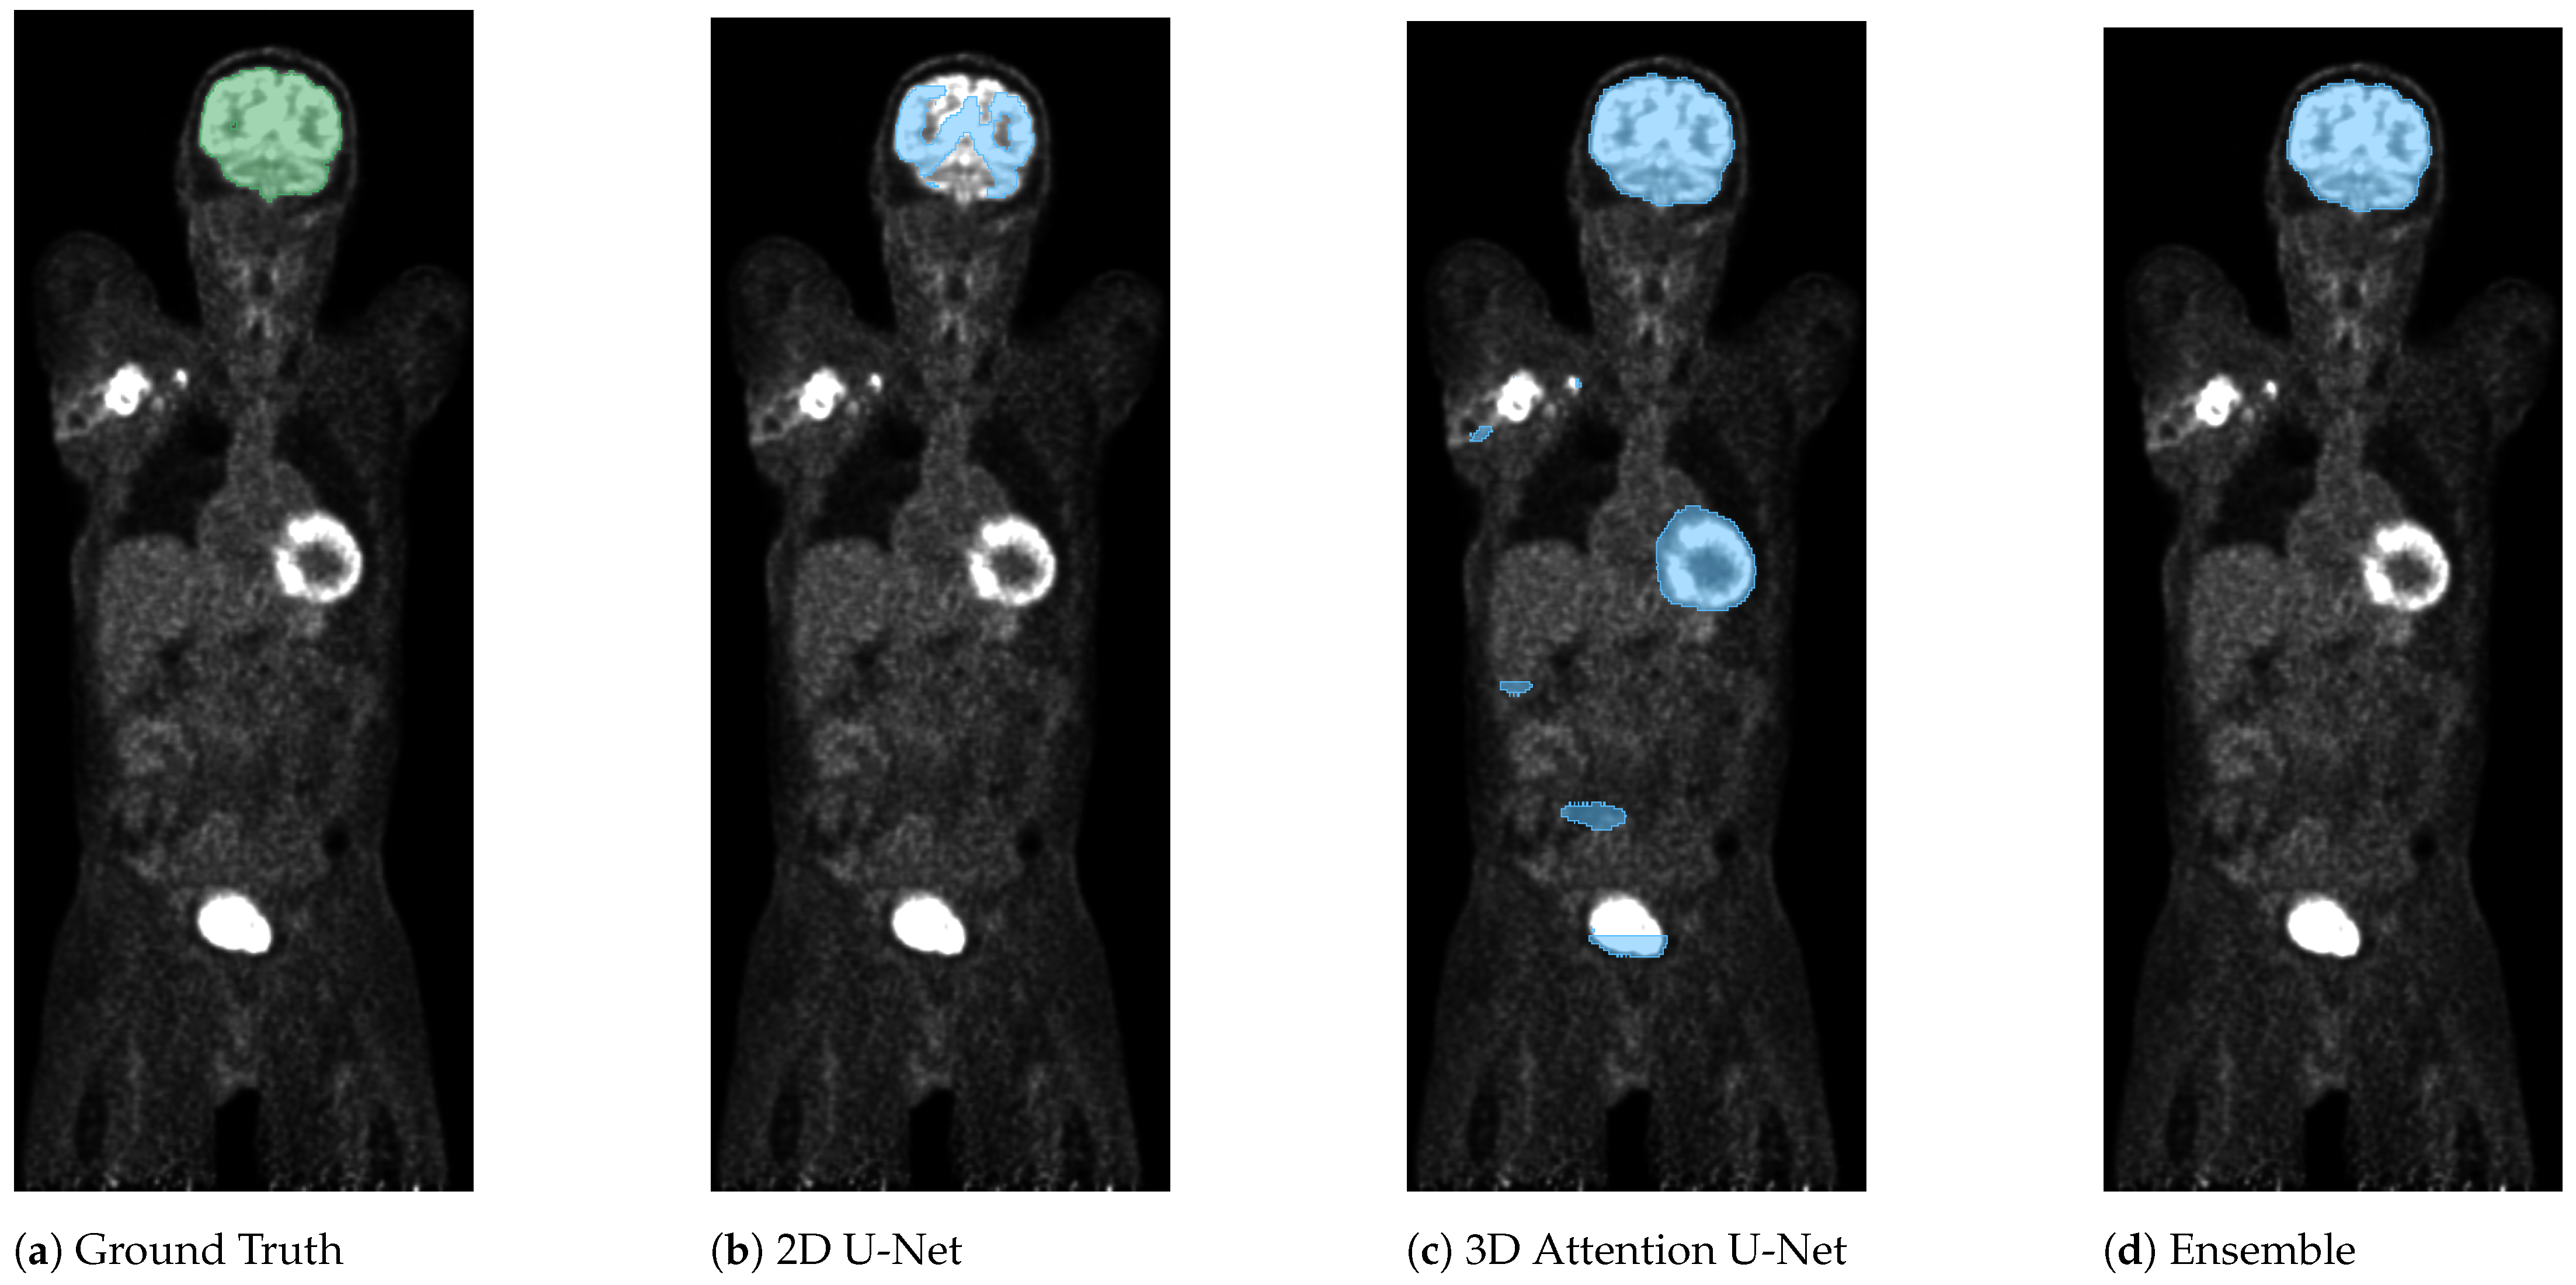

3. Results